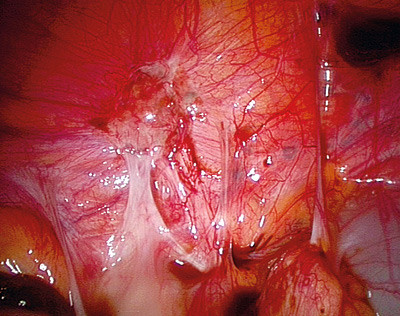

Smerter assosiert med endometriose er ikke alltid relatert til sykdommens utbredelse. Det er ulike teorier for smertemekanismene ved endometriose. Aktive endometrioseimplantater kan produsere humorale faktorer som vekstfaktorer og cytokiner, implantatene kan forårsake smerter på grunn av blødning (fig 2), og de kan irritere og infiltrere nerver i bekkenet. Alle disse mulige mekanismene kan føre til bekkensmerter (9, 10).

Diagnostisk laparoskopi er gullstandarden for identifisering av peritoneal endometriose. Påvisning av implantater bør dokumenteres adekvat, fortrinnsvis bildediagnostisk, eventuelt med biopsi og histologisk verifisering av implantatene. Det er viktig at hele bukhulen inspiseres grundig, da implantatene kan ha mange ulike lokalisasjoner, også i øvre del av abdominalhulen. Operativ laparoskopi ved peritoneal endometriose innebærer reseksjon eller destruksjon av alle påviste endometrioseimplantater. Det kliniske resultatet etter laparoskopisk kirurgi ved peritoneal endometriose synes mer avhengig av operatørens dyktighet og erfaring enn av operasjonsteknikk og valg av energikilde.